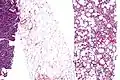

Histopathology of liposarcomas

Fig. 1 Micrograph of bone formation in a liposarcoma tumor

Fig. 2 Micrograph of a dedifferentiated liposarcoma tumor

Fig. 3 Lower-power micrograph of myxoid liposarcoma tumor- Fig. 4 Higher-power micrograph of myxoid liposarcoma tumor

Histopathologically, ALT/WDL tumors are divided into adipocytic/lipoma-like, sclerosing, and inflammatory variants with adipocyte/lipoma-like being the most common. Adipocytic/lipoma-like ALT/WDL tumors consist of lobules of mature fat cells variably intersected with irregular fibrous septa (see the adjacent H&E stained photomicrograph). Sclerosing ALT/WDL tumors, the second most common variant, develop primarily in the retroperitoneal and paratesticular areas; it consists of scattered, atypical stromal cells within a collagenous (i.e. collagen-containing) stromal tissue background. Rare vacuole-containing lipoblasts populate this tissue. Inflammatory ALT/WDL tumors are the rarest variant. they occur most frequently in the retroperitoneum and consists of chronic inflammatory cells, e.g. lymphocytes and plasma cells plus occasional lymph node-like follicles interspersed throughout a tissue background containing fat cells.[14]

The histopathological appearance of DDL tumors (see Fig. 2 in the below Histopathology of liposarcomas section) varies widely but most frequently exhibits features of undifferentiated pleomorphic sarcomas (which are tumors densely populated with variably sized and shaped cells containing variability sized and shaped nuclei) or spindle cell sarcomas (which are tumors consisting of spindle-shaped cells in a connective tissue background). Different parts of DDL tumors often show variations in the appearances of their background connective tissues: these tissues may be myxoid (i.e. consisting of a clear, mucus-like substance which when stained using a standard H&E stain method appears more blue or purple than the red color of normal tissues) or myxocollagenous (i.e. high collagen fiber content in a myxoid background), and, in ~5% of cases, have areas of osteoid (see Fig. 1 in the below Histopathology of liposarcomas section) or cartilaginous material. The tumors also show large variations in their cell contents. For example, up to 10% of DDL tumors have areas with ALT/WDL histopathology [8] and rare cases of DDL have areas containing meningothelial-like whorls of flat cells.[24][25]

Histopathologic analyses of MLS (see Figs. 3 and 4 in the below Histopathology of liposarcomas section) reveals cells scattered throughout a myxoid matrix (i.e. a connective tissue background that appears more blue or purple than the red color of normal connective tissue when these tissues are properly prepared, H&E stained, and viewed microscopically). These cells are lipoblasts, some of which are signet ring-shaped (a shape suggesting that the cell may be neoplastic), oval-shaped, or round-shaped.[40] MLS tumors may be hypercellular and contain solid sheets of round cells that comprise at least 5% of all cells or low cellularity populated with cells that have bland nuclei and <5% round cells in a background of curving capillaries resembling a chicken-wire pattern. Tumors that contain at least 5% round cells are classified as high-grade while those with <5% round cells are classified as low-grade.[39] High-grade MLS tumors typically take a more aggressive clinical course than low-grade MLS tumors.[40]